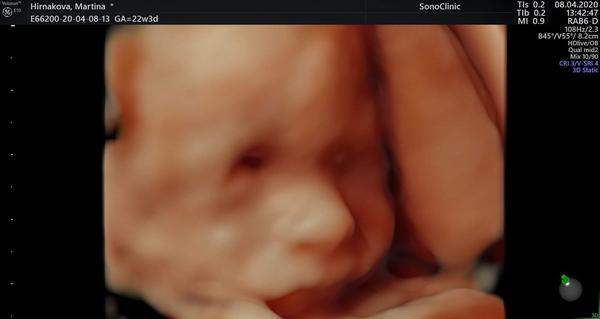

Ahojte baby, podobalo sa bábätko po narodení z foto na 3D/4D? Môžte pridať aj foto pred a po 😄

@martinahrnkv nie nepodobalo, moja mala bola este skaredsia ako na fotke z utz 😂🙈❤️a tam bola velmi skareda, dokonca vsetci tipovali ze to je chlapec, este tak par dni bola cela dokrcena, nostek krivy a plochy, jedna dierka vscsia ako druha, akoze uz som v mysli sporila na plastku😂🙈 chvalabohu dnes ma rok a pol a krajsie dievca som nevidela❤️❤️❤️

@bielavila som sa teraz zasmiala 😂😂😂 môj vyzerá na fotkách z rovnakého ultrazvuku v jeden deň na každej inak 🤔😄

@martinahrnkv tvoj vyzera krasne, moja vyzerala sko ufon, ozaj som sa bala ukazat foto muzovi😂